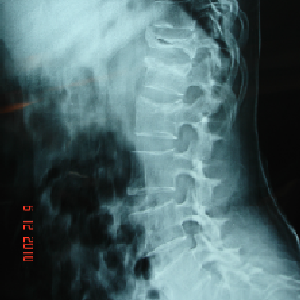

A very young pt of 25 years old, belonging to very good family, an engineer, had

tuberculosis of cervical

spine with destruction of C7 vertebra

if he would not get urgent attention and surgery, he could have landed up in developing

paraplegia

he was operated from front of the neck, a new vertebra(tricortical bone graft) was

put and fixed with plate

now he is doing very well in his life

Paeditric Koch’s - Spine